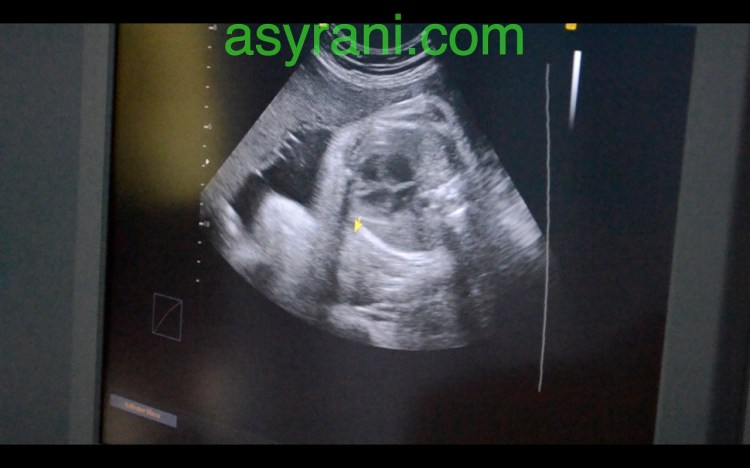

Anak panah menunjukkan Four Chamber jantung baby

Gambar Four Chamber jantung yang lebih jelas

Usus dan perut baby(yang berwarna gelap tersebut)

Pundi Kencing yang dah berfungsi menurut kata Dr., jadi buah pinggang juga sudah berfungsi dengan baiknya

Jantina baby iaitu perempuan (kelihatan jelas disitu)